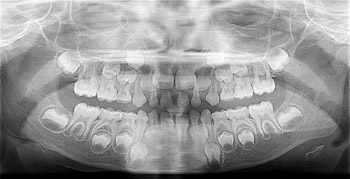

Why Take Dental X-Rays on a Child?

Posted .

There would be no need for dental X-rays if all dental issues existed above the gum line. However, this is simply not the case. Damage, decay and infections that cannot be seen by the naked eye are only visible on X-rays. Dental X-rays are the only way to get a complete view of your child’s mouth. It is important to... read more »